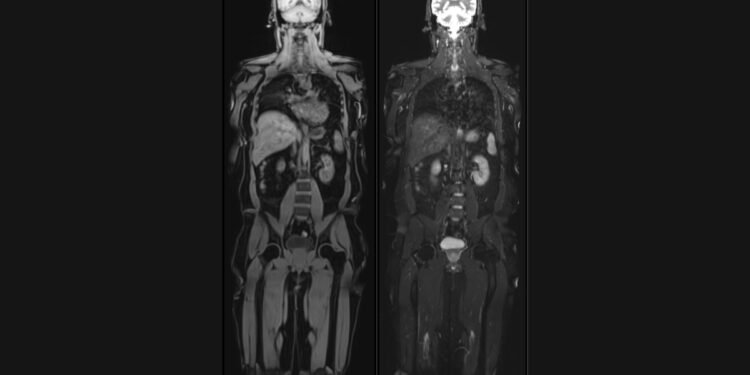

Vital Full Body MRI aims to detect potential health issues at their earliest stages, including early-stage cancers, aneurysms, spinal degeneration, disc bulges, and abnormalities in the brain, abdomen, and chest. The scans utilize cutting-edge technology to provide detailed, high-resolution images, enabling early diagnosis and intervention, thereby improving treatment outcomes.

Unique offerings of Vital MRI are – Brain volume analysis, Liver fat and Visceral fat quantification by MRI and Calcium scoring CT to assess heart attack risk. Brain volumetry analysis, generating a ‘Brain Age’ report that compares an individual’s brain health to their chronological age. This valuable insight can help individuals understand their cognitive well-being and take proactive measures to maintain brain health and prevent dementia.